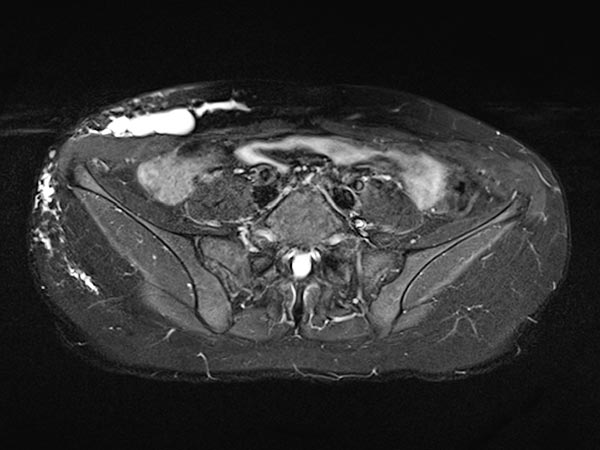

Transverse T1-weighted, fat-suppressed MRI after contrast administration shows only minimal enhancement of the thin walls of the lymphatic malformation. This is typical of a lymphatic malformation, as the liquid in the cysts (lymph) does not enhance.